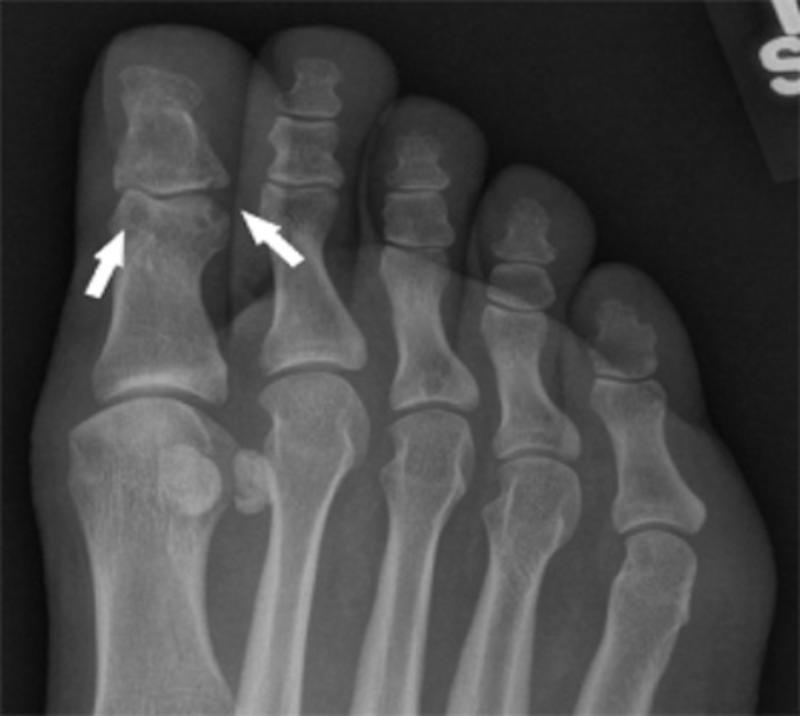

Gout — FOOT & ANKLE CENTERS What Is Therapeutic Target For Gout Patients The following recommendations were strongly recommended by two or more cpgs: Treatment strategies have appropriately focused on the prevention of gout flares, but it is increasingly recognized that. Because the pathogenesis of gout is strongly related to. Serum uric acid (sua) levels should be. Gout management involves two broad aspects: Gout is a chronic disease with a high burden of. What Is Therapeutic Target For Gout Patients.